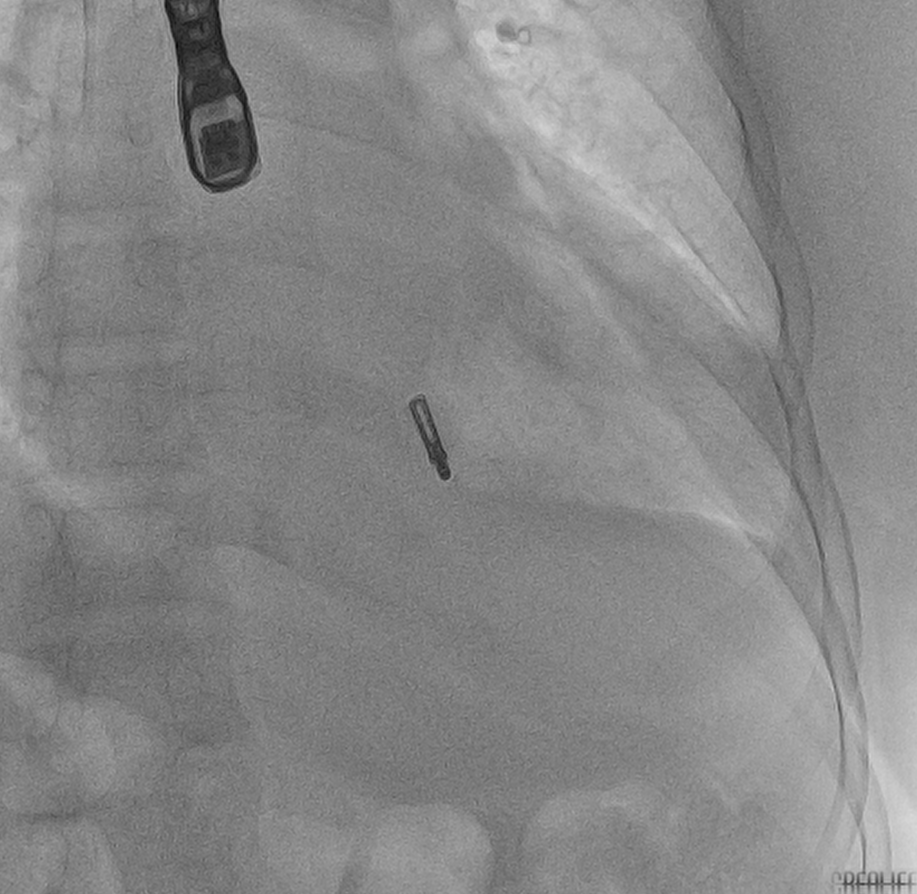

在患者全麻状态下经股静脉置管、经食道超声(TEE)引导房间隔穿刺后置入导引鞘管,手术团队将夹合器精准送达二尖瓣反流区。在TEE及X线引导下,手术团队利用二尖瓣夹(Mitraclip)准确捕获二尖瓣叶,试夹闭后经过超声证实夹闭有效,释放成型夹。术后超声评估,二尖瓣口仅见轻微反流,反流情况明显改善,患者各项生理指标正常,Mitraclip手术高质量完成。患者于术后第3天顺利出院,出院前检查患者二尖瓣反流各项参数指标恢复都超出了预期效果。

经导管二尖瓣钳夹术使用特制的二尖瓣夹合器,经股静脉进入,穿刺房间隔,进入左心房及左心室,在三维超声及DSA(数字减影血管造影)引导下,使用二尖瓣夹合器夹住二尖瓣前、后叶反流部位,使二尖瓣在收缩期由大的单孔变成小的双孔,从而明显减少二尖瓣反流,阻止心脏扩大,改善心功能。其治疗二尖瓣返流已被证实是一种无需开放式心脏手术的新型、微创、安全的治疗策略。